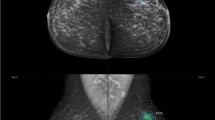

A thirty-eight-year-old lady presented with a right breast lump. Mammography revealed right UOQ focal asymmetry and parenchymal distortion as well as internal amorphous calcifications (a). US revealed right breast UOQ prominent glandular tissue with complicated cyst (b). AI Software revealed no evidence of highlighted areas with PoM scoring less than 10 (low) indicating benignity (a). The final diagnosis was fibrocystic disease with periductal mastitis